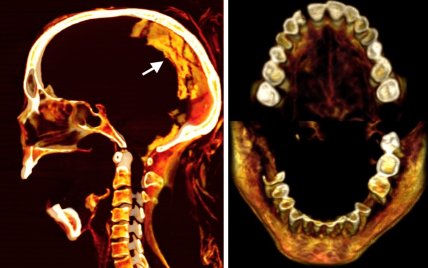

Предположительно, на момент смерти женщине было около 48 лет и она страдала легким артритом позвоночника. Также у нее не хватало нескольких зубов, которые она утратила еще при жизни. Останки "Кричащей женщины" сейчас хранятся в Египетском музее в Каире, а гроб и кольца — в Метрополитен-музее в Нью-Йорке.